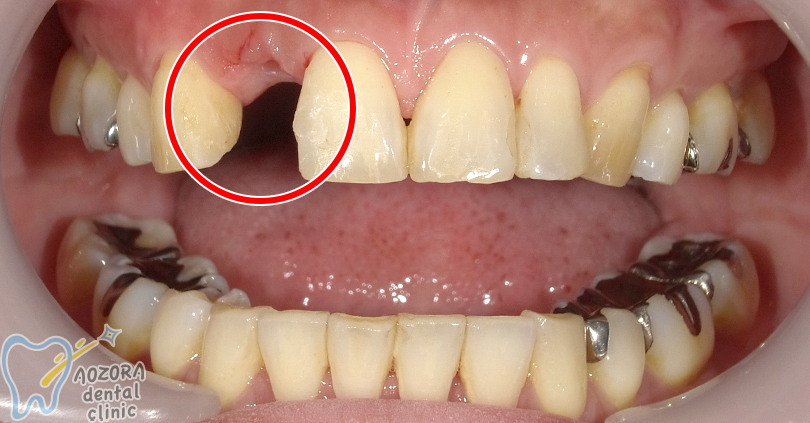

40代 女性の場合

主訴

右上2番目、歯の根っこが割れてしまい、抜かないといけなくなってしまった。周りの歯を削りたくない。

治療期間 約6ヶ月

歯を抜いてから骨がしっかり治るまで、3ヶ月待ってから、

インプラント治療、被せ物をしました。

術前

術後